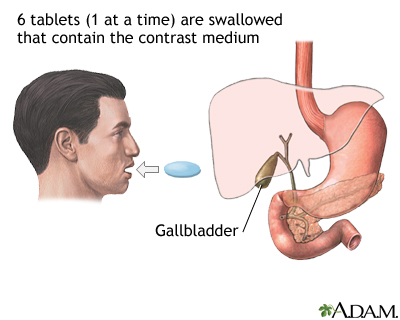

Imaging tests can show gallstones or inflammation. You may have one or more of these tests: